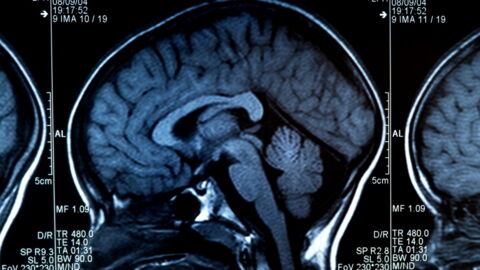

According to a study published in the Alzheimer's and Dementia medical journal, Alzheimer's disease affects a part of the brain that is responsible for keeping people awake, which may explain why people with this condition take so many naps.

An increase in the number of naps might be one of the first symptoms to appear in patients, before memory loss. The study was conducted by researchers at the University of California.

The scientists also highlighted the tau protein and its role in the development of the disease. This is not the first study to do so, but more specific research on the subject (because until now, studies have focused more on the amyloid protein) is making it possible to learn more about this protein's role in the development of this disease.

Lea Grinberg, co-author of the study and professor of neurology, said: 'Our work shows definitive evidence that the brain areas promoting wakefulness degenerate due to accumulation of tau, not amyloid protein, from the very earliest stages of the disease.'